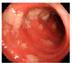

Nye

Antibiotikabehandling i sykehus1

anbefaler

Faktorer som kan øke risiko for residiv er1:

• Immunsvikt

• Tidligere CDI

• Sykehusopphold siste 3 måneder

• Protonpumpehemmer

• Høy alder

Utvalgt produkt- og sikkerhetsinformasjon DIFICLIR (fidaksomicin) 200 mg tabletter og granulat til mikstur, 40 mg/ml

Indikasjoner: For behandling av Clostridioides difficile-infeksjoner (CDI), også kjent som C. difficile-assosiert diaré (CDAD).

Tabletter: Hos voksne og pediatriske pasienter med en kroppsvekt på minst 12,5 kg. Granulat: Hos voksne, ungdom og barn 0 - < 18 år. For både tabletter og granulat skal det tas hensyn til offisielle retningslinjer for korrekt bruk av antibakterielle midler.

Vanligste bivirkninger: Vanlige: Forstoppelse, kvalme, oppkast.

Vanligste alvorlige bivirkninger: Overfølsomhetsreaksjoner inkl. alvorlig angioødem.

Interaksjoner: Forsiktighet utvises ved samtidig bruk av potente P-gp-hemmere.

Kontraindikasjoner: Overfølsomhet for innholdsstoffene.

Forsiktighetsregler: Fidaksomicin bør brukes med forsiktighet ved kjent allergi mot makrolider. Hvis det oppstår en alvorlig allergisk reaksjon, skal legemidlet seponeres og egnede tiltak igangsettes. Bør brukes med forsiktighet ved pseudomembranøs kolitt eller fulminant eller livstruende CDI, ved nedsatt lever- og nyrefunksjon. Granulat bør brukes med forsiktighet hos spedbarn < 6 måneder/< 4 kg.

Graviditet, amming og fertilitet: Graviditet: Det anbefales å unngå bruk under graviditet. Amming: Det må tas en beslutning om amming skal opphøre eller behandling avstås fra, basert på nytte-/risikovurdering. Fertilitet: Dyrestudier indikerer ingen effekt på fertilitet.

Dosering: Tabletter: Voksne og barn >12,5 kg: Standard dosering: Anbefalt dose er 200 mg (1 tablett) administrert 2 ganger daglig (1 tablett hver 12. time) i 10 dager. Utvidet pulsdosering: 200 mg tabletter administreres to ganger daglig for dag 1–5 (ingen tablett på dag 6) og deretter én gang daglig annenhver dag for dag 7–25. Hvis en dose blir glemt, skal den glemte dosen tas så snart som mulig, men hvis det snart er tid for neste dose, skal tabletten hoppes helt over. Granulat: Voksne: Anbefalt dose er 200 mg (5 ml) 2 ganger daglig (5 ml hver 12. time) i 10 dager. Ungdom og barn 0 - < 18 år: Anbefalt dose baseres på kroppsvekt og tas 2 ganger daglig (1 dose hver 12. time) i 10 dager.

Administrering: Tabletter: Kan tas med eller uten mat. Svelges hele sammen med et glass vann.

Granulat: Rekonstitueres av farmasøyt eller helsepersonell. Tas peroralt, eller via sonde.

Pakninger og priser: Tabletter 20 stk. (blister) kr 18 099,90. Granulat til mikstur: 1 stk. (glassflaske) kr 18 288,90.

Reseptgruppe C.

Basert på SPC godkjent av SLV/EMA: 12.12.2022.

PM-DG-NO-00003

For utfyllende informasjon om dosering, forsiktighetsregler, interaksjoner og bivirkninger – se felleskatalogen.no

Tillotts Pharma AB | Gustavslundsv. 135, 167 51 Bromma, Sverige | Tel: +46 8-704 77 40 | nordicinfo@tillotts.com | www.tillotts.se

Referanse: 1. https://www.helsedirektoratet.no/retningslinjer/antibiotika-i-sykehus/infeksjoner-i-abdomen#clostridioides-difficile-infeksjon. Sist faglig oppdatert 01.03.2022.

PM-DT-NO-0004. THAU

retningslinjer

at Dificlir (fidaksomicin) vurderes til behandling av Clostridioides difficile-infeksjon (CDI) hos pasienter med høy risiko for residiv1